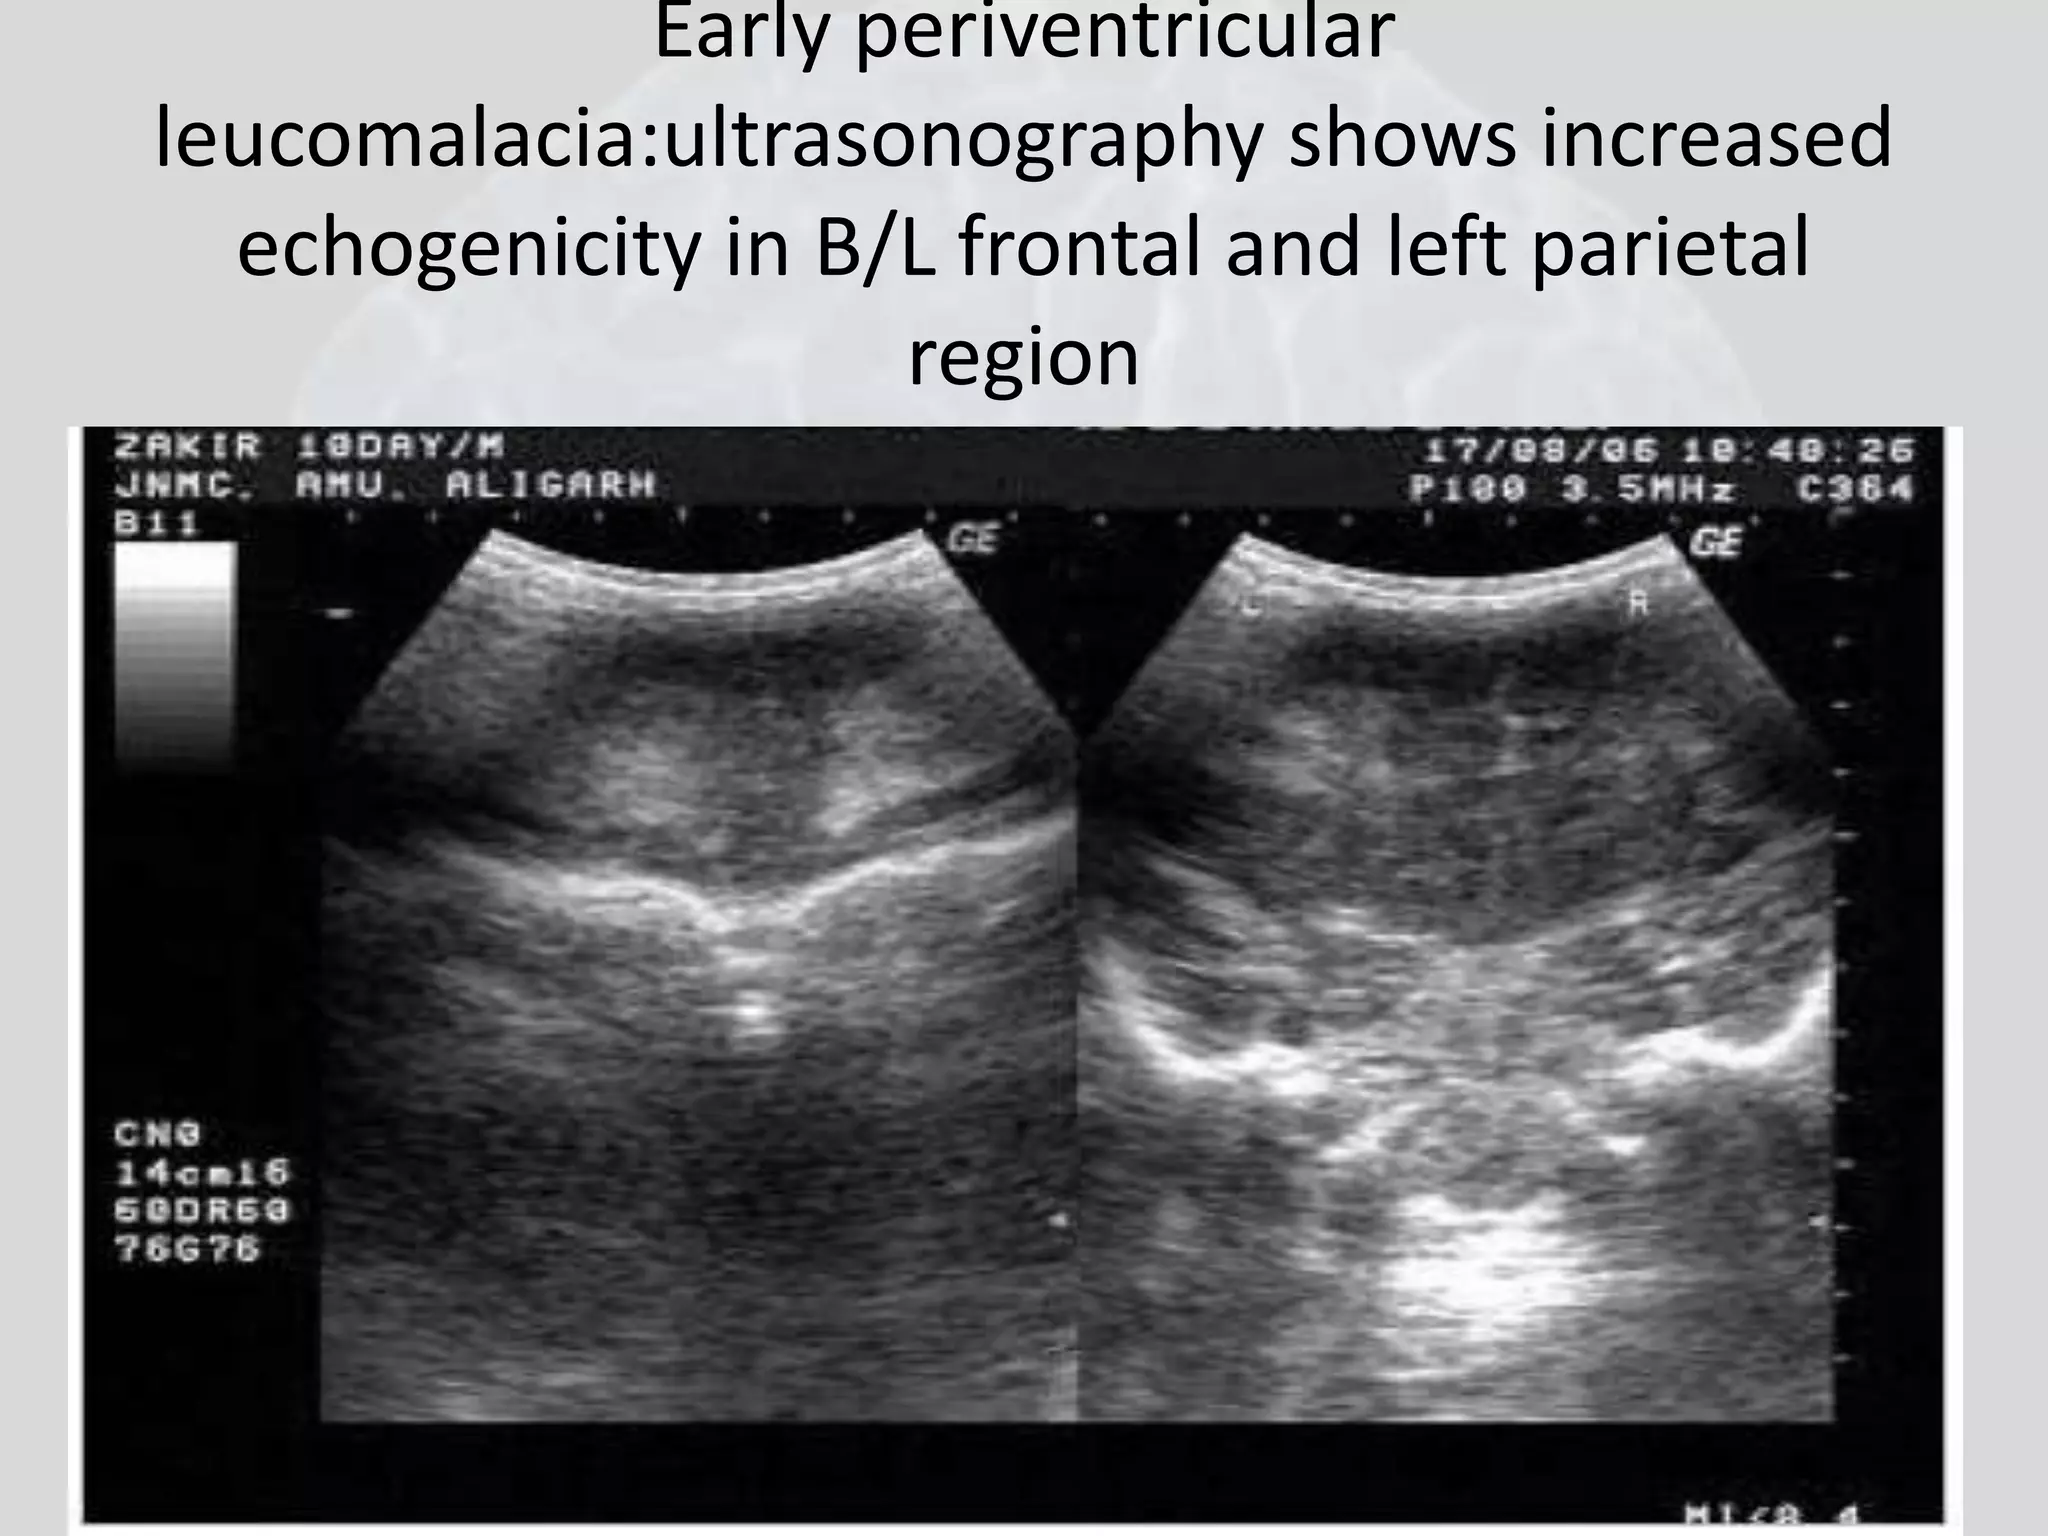

Early periventricular

leucomalacia:ultrasonography shows increased

echogenicity in B/L frontal and left parietal

region

Early periventricular leucomalacia:ultrasonographyshows increased echogenicity in B/L frontal and left parietal region